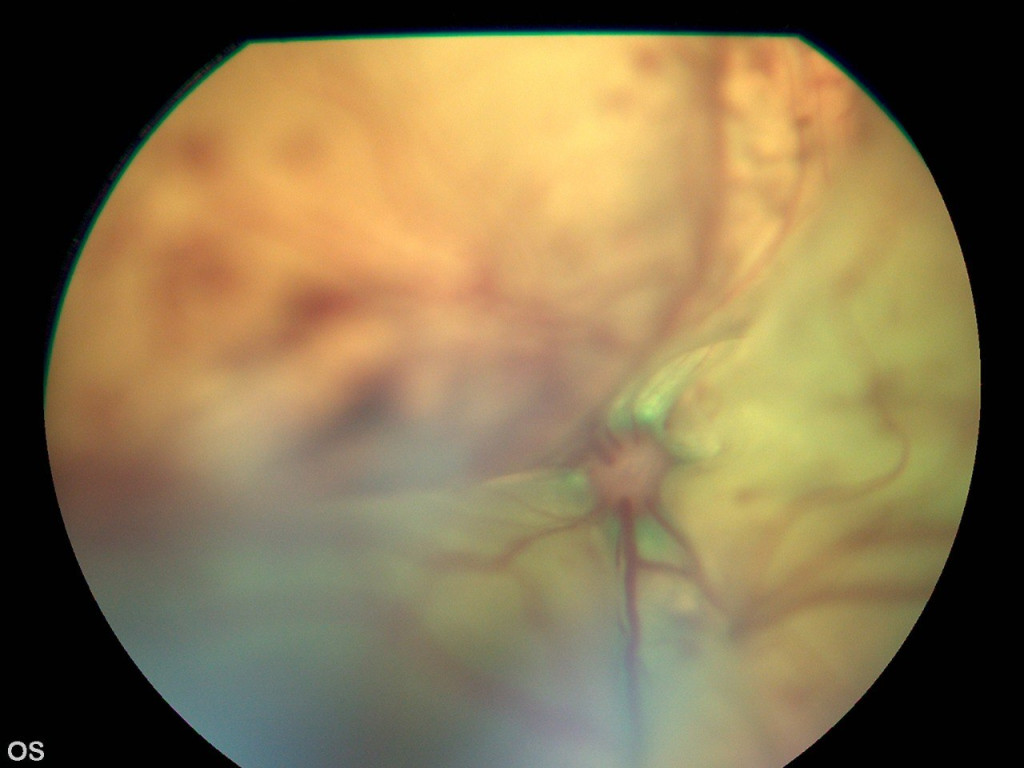

Слепота у животных – это полная или частичная утрата зрительной функции. Она может быть обусловлена патологией глазного яблока, а также патологиями различных структур нервной системы4.Вне зависимости от локализации проблемы слепота может быть приобретенной (фото 1) или врожденной (фото 2).

Врожденная слепота чаще всего обусловлена аномалиями развития глаз, при которых могут поражаться хрусталик, сетчатка и диск зрительного нерва. Также она может быть связана с некоторыми системными заболеваниями, например с врожденной тетраплегией8. В большинстве случаев врожденная слепота является необратимой, а терапевтические меры направлены на создание благоприятной среды для пациента, обеспечение его комфорта и профилактику возможных осложнений.